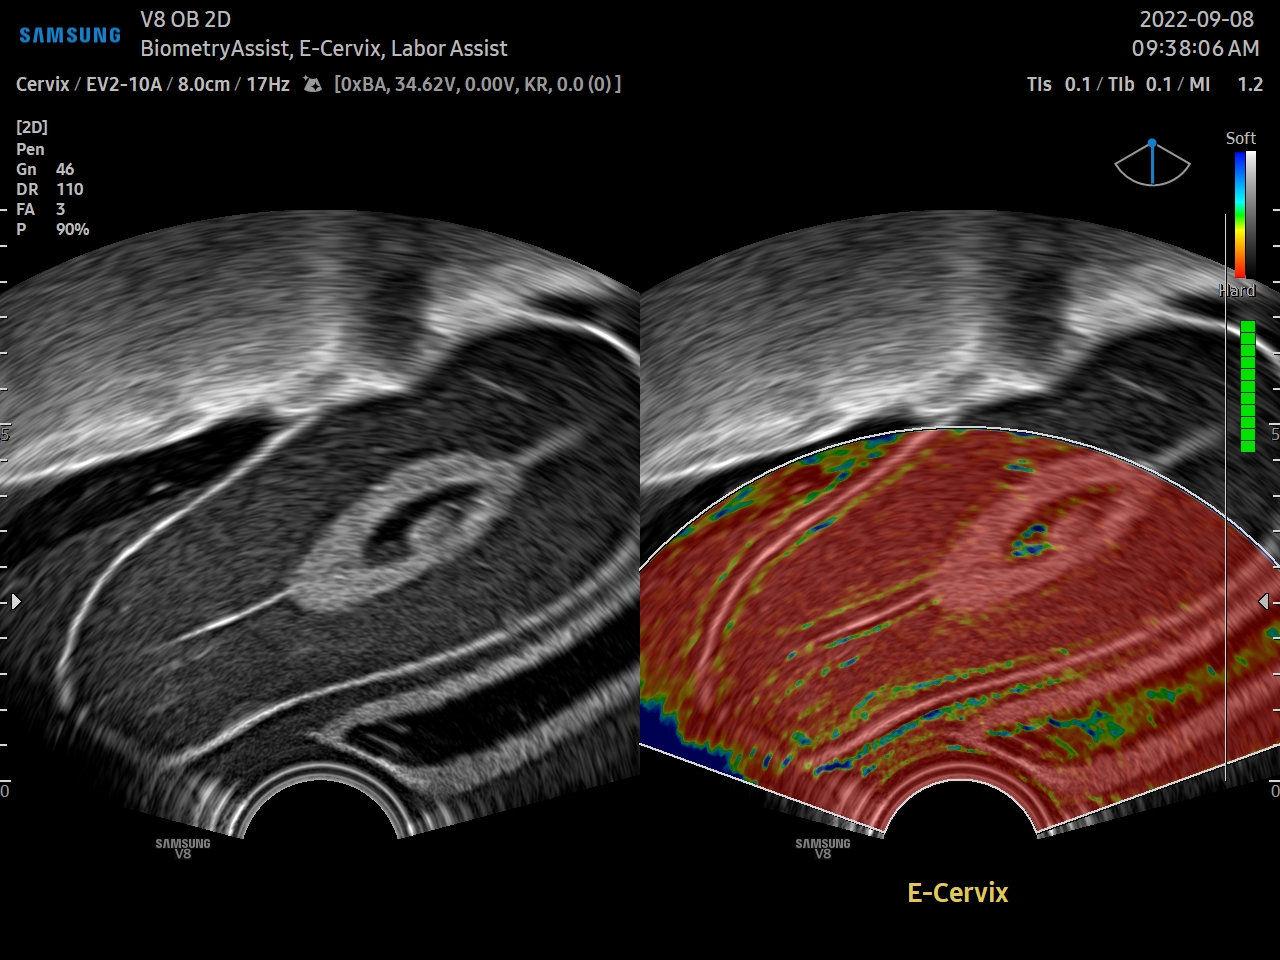

El sistema de ultrasonido V8 mejora el flujo de trabajo y el rendimiento de los pacientes en la atención médica de la mujer. Gracias a las funciones premium Crystal Architecture™ e Intelligent Assist de Samsung, el V8 ayuda a agilizar los procesos y a aumentar la confi anza incluso en exámenes femeninos complejos, además de ayudar a comunicar los resultados fácilmente a las pacientes.